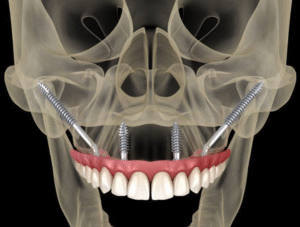

Trong quá trình điều trị, Bác sĩ Cang Hồng Thái luôn lắng nghe và hiểu rõ nhu cầu của bệnh nhân, đồng thời giúp giải quyết các vấn đề tâm lý mà bệnh nhân đang gặp phải. Mọi phương án điều trị được thiết kế sao cho ít xâm lấn gây tổn thương cho răng thật, mô mềm và xương hàm nhất có thể, để mang lại trải nghiệm điều trị răng miệng tốt nhất cho bệnh nhân.

Bác sĩ Chuyên khoa I Cang Hồng Thái hiện là Giám đốc Nha Khoa Đông A và có hơn 20 năm kinh nghiệm trong lĩnh vực cấy ghép Implant, chỉnh nha, phục hình răng thẩm mỹ. Ông đã làm việc tại các bệnh viện lớn như Răng Hàm Mặt và Đại học Y Dược TPHCM.

Mỗi năm, có hơn 4000 khách hàng từ trong và ngoài nước đến điều trị thành công với bác sĩ Thái. Trong quá trình tư vấn và điều trị, ông luôn lắng nghe nhu cầu của bệnh nhân, giúp họ thoải mái và hiệu quả nhất. Mọi kế hoạch điều trị của ông đều dựa trên nghiên cứu kỹ lưỡng, nhằm bảo tồn răng gốc tối đa.

Với quan điểm “Không có phương pháp tốt, chỉ có phương pháp phù hợp nhất”, mỗi khách hàng được bác sĩ Thái tiếp nhận đều có trải nghiệm điều trị răng miệng tuyệt vời, xứng đáng với niềm tin và chi phí đã bỏ ra.